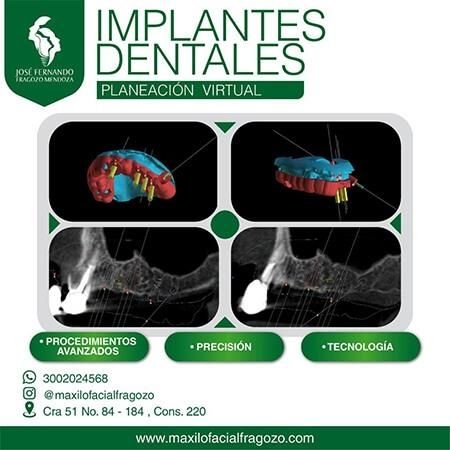

José Fernando Fragozo Mendoza es un odontólogo especializado en Cirugía Oral y Maxilofacial por la Universidad El Bosque de Bogotá. Con una atención personalizada, ofrece cirugía oral y maxilofacial, así como implantes dentales respaldados por el método científico y tecnología de vanguardia.

- Curso diagnóstico y planificación en implantología - , 2021

Me realice 2 implantes dentales. Un implante en la parte superior derecha y el otro implante en la parte inferior izquierda. El Dr. Fragozo fue muy paciente y profesional. La recuperación después de los implantes fue muy satisfactoria. El Dr. estuvo muy pendiente de mi. Hoy en día que tengo mis dos implantes no he tenido ningún tipo de dolor ni inconvenientes. Muy satisfecha con el trabajo del Dr. Lo recomiendo a un 100% para implantes dentales.